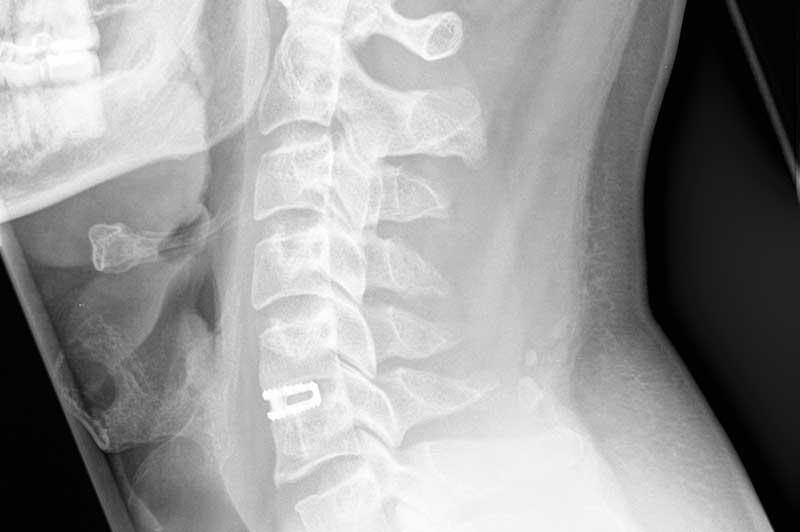

Seitliches Röntgenbild nach einer Dekompression und Fusion der Halswirbelsäule mit einem Cage (Abstandhalter) im Segment C5/C6.

Anschliessend wird ein sogenannter Cage (Abstandhalter) eingesetzt, der zuvor mit körpereigenem Knochenmaterial und Spenderknochenmaterial gefüllt wurde. Es folgen eine Röntgenkontrolle und der Wundverschluss.